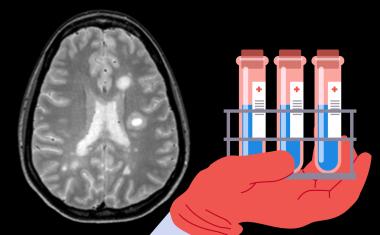

Wie können Roboter und Menschen in Zukunft bestmöglich im OP zusammenarbeiten? Das haben Forschende der Technischen Universität München (TUM) und des TUM Klinikums im Forschungsprojekt ForNeRo untersucht.